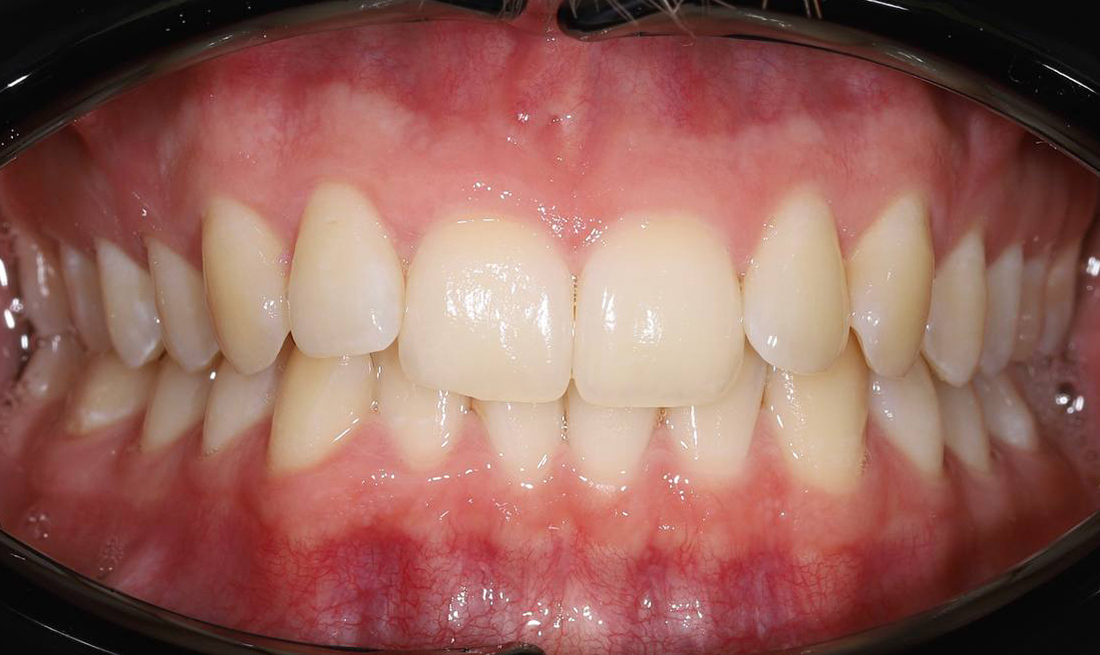

Примеры работ